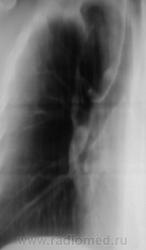

Боковая проекция.